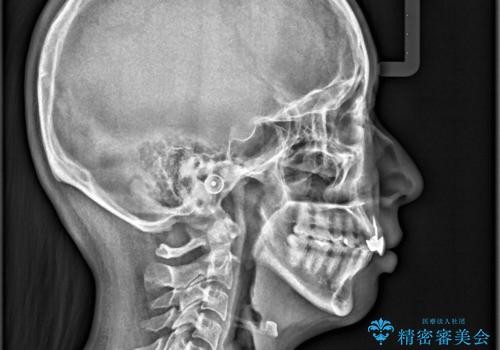

- ワイヤーで矯正した後戻りをマウスピースで治そうとしたが、使えなかったため再度ワイヤー矯正希望で来院されました。

矯正としてはマウスピースでできましたが、患者さんの希望でワイヤー(ハーフリンガル)で矯正を行いました。

右下1が歯肉退縮していたため、アーチを拡げないように歯と歯の間を削って隙間をあけて並べています。